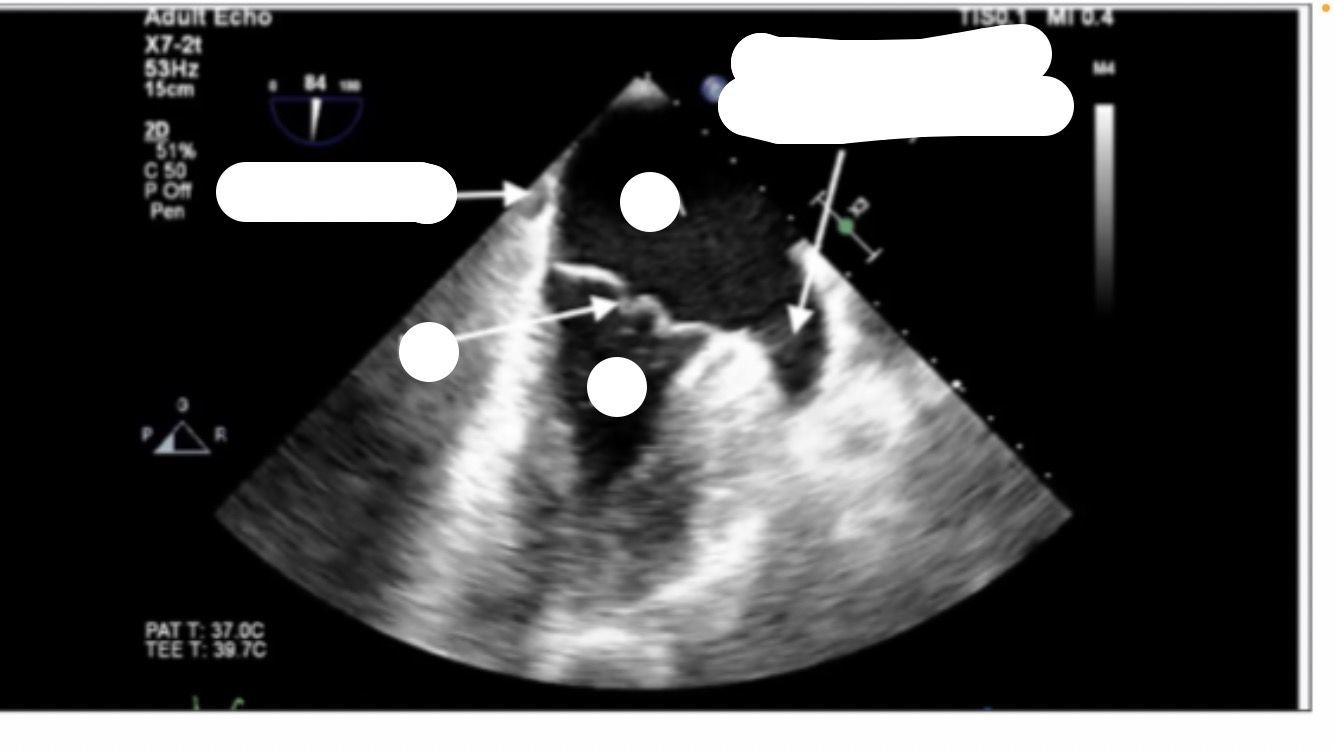

Bicaval view

mid-esphageal bicaval